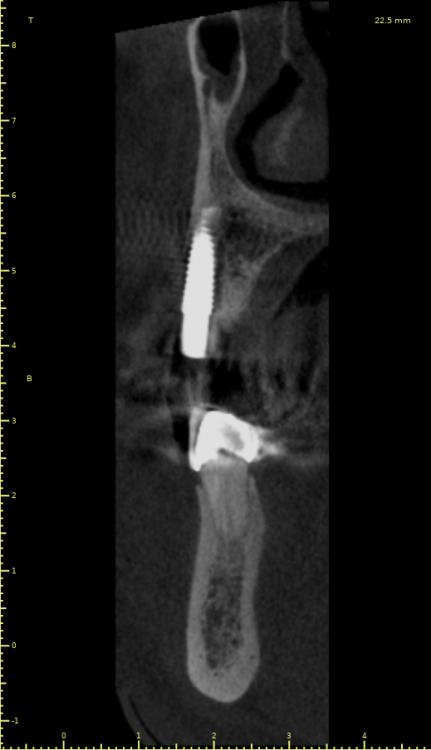

Женька Опубликовано 21 июля, 2021 Автор Поделиться Опубликовано 21 июля, 2021 3 месяца минуло... клык на торке 30 неприятные ощущения второй премоляр на 10 и подвижность... отправил на кт. Всё насмарку... Ссылка на комментарий

Борис80 Опубликовано 21 июля, 2021 Поделиться Опубликовано 21 июля, 2021 премоляр в любом случае недозаглубитом болеет... Ссылка на комментарий

Карен Аванесов Опубликовано 21 июля, 2021 Поделиться Опубликовано 21 июля, 2021 2 часа назад, Женька сказал: 3 месяца минуло... клык на торке 30 неприятные ощущения второй премоляр на 10 и подвижность... отправил на кт. Всё насмарку... Спишем на профессиональные вредности пациента курение и двухсот граммовые жимы на грудь , при переустановке, будет и легче и лучше. Гарантии какие были? Ссылка на комментарий

Женька Опубликовано 22 июля, 2021 Автор Поделиться Опубликовано 22 июля, 2021 @Карен Аванесов скажем так. Один из этих имплантатов я уже переустанавливал по гарантии (то есть с другой стороны год назад ставил 2, выжил 1, этот 1 и пошел на замену по гарантии, но на другую сторону). Так что теперь планирую достать и просто напросто всё зашить и ждать (вопрос к коллегам, сколько вы ждёте обычно?). Затем по двухэтапному протоколу, без всяких формиков одномоментных поставить и зашить под заглушки... Иначе видимо это работать не будет. Касаемо финансов это ёще одна бесплатная переделка (ну расходники не в счёт) Ссылка на комментарий

Женька Опубликовано 2 августа, 2021 Автор Поделиться Опубликовано 2 августа, 2021 2.5 с тупым перкуторным звуком И вишенка, нет АРБУЗИЩЕ, на торте 2.3 в соседней теме в ортопедии посоветовали перестать уничтожать людям зубы, тоже самое помоему можно сказать и по хирургии... Правильно же понимаю, что протезировать такой (2.3) не стоит. Даже если торк выдержит в 35 чревато проблемами после установки постоянной ортопедии. Ссылка на комментарий